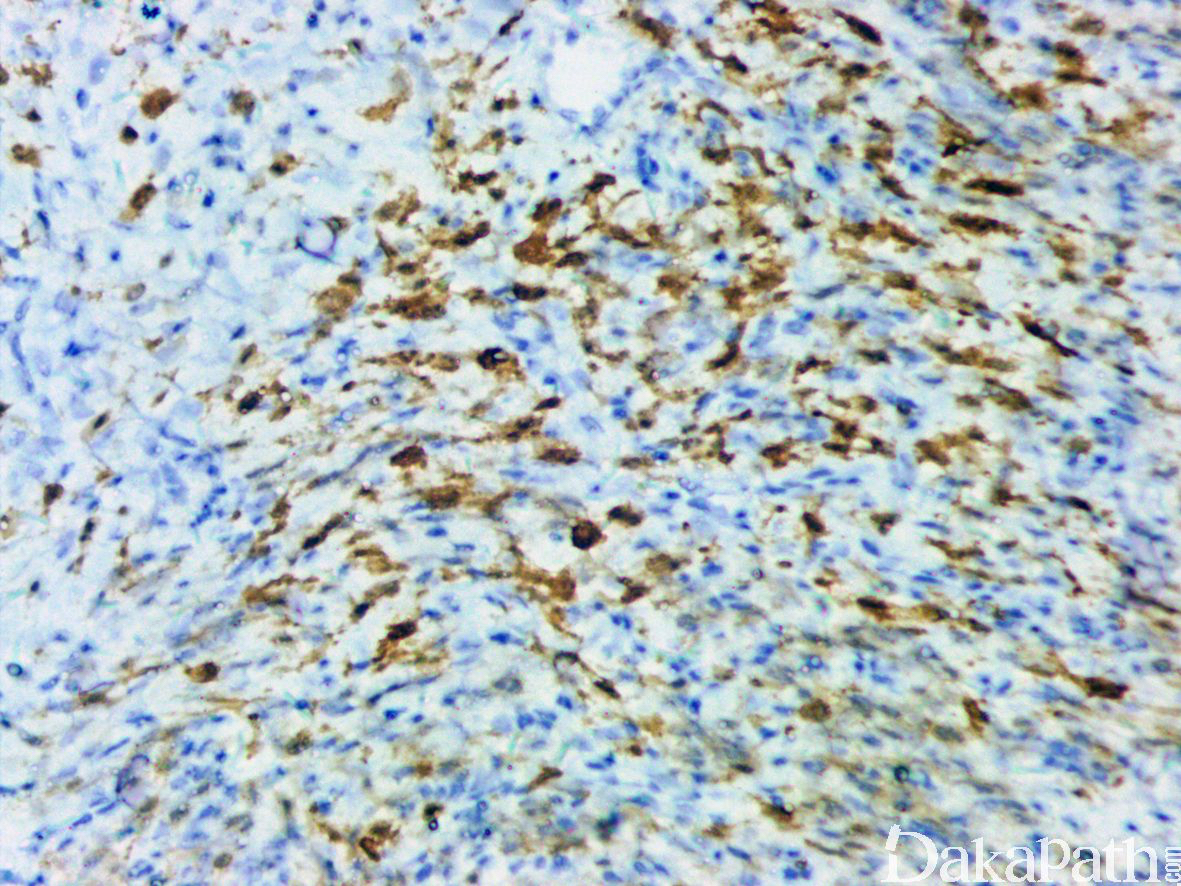

免疫组织化学染色:

多灶性的强表达 S100 蛋白和 CD34,NTRK1 基因重排的病例弥漫表达 NTRK1 蛋白;少数肿瘤可局灶表达 SMA,一般不表达 desmin, EMA, GFAP、SOX10,HMB45,STAT6 等,H3K27me3 表达无丢失。